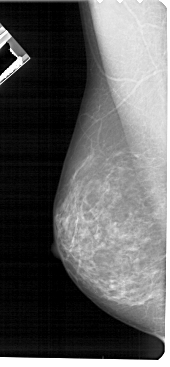

A_1715_1.RIGHT_MLO

RIGHT_MLO LINES 5491 PIXELS_PER_LINE 2386 BITS_PER_PIXEL 12 RESOLUTION 43.5 OVERLAY